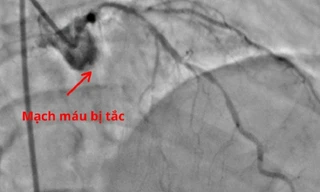

Chết lâm sàng vì bỏ qua dấu hiệu cảnh báo nhồi máu cơ tim cấp